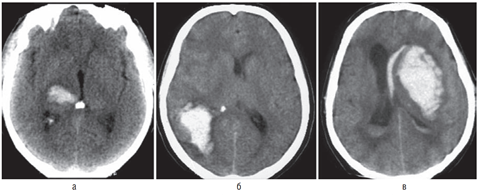

Тяжесть состояния больного непосредственно после кровоизлияния и в последующие дни определяется выраженностью общемозговых и дислокационных симптомов, в свою очередь обусловленных объемом внутримозговой гематомы и ее локализацией. При обширных кровоизлияниях и кровоизлияниях глубинной локализации в клинической картине довольно быстро появляется вторичная стволовая симптоматика, обусловленная дислокацией мозга. Для кровоизлияний в ствол мозга и обширных гематом мозжечка характерно быстрое нарушение сознания и витальных функций. Наиболее тяжело протекают кровоизлияния с прорывом в желудочковую систему (рис. 12.3). В большинстве случаев для них характерны появление горметонических судорог, гипертермии, менингеальных симптомов, быстрое угнетение сознания, развитие стволовых симптомов. В то же время, если не происходит окклюзии излившейся кровью ликворопроводящих путей, в частности сильвиева водопровода и IV желудочка, попадание крови в ликворную систему может не сопровождаться клиническим ухудшением.

img92

Рис. 12.3. Большая смешанная гематома глубинных отделов левого полушария с прорывом в III желудочек, частичным заполнением кровью боковых желудочков, выраженная дислокация мозга вправо (компьютерная томограмма)

Геморрагический инсульт следует дифференцировать прежде всего от ишемического, составляющего до 80–85% всех инсультов. Поставить точный диагноз необходимо, чтобы как можно раньше начать соответствующую терапию. Дифференциальная диагностика по клиническим данным не всегда возможна, поэтому необходимо госпитализировать больных с диагнозом «инсульт» в стационары, оснащенные КТ- или МРТ-оборудованием. Для ишемического инсульта характерны более медленное нарастание общемозговых симптомов, отсутствие в большинстве случаев менингеальных симптомов, в ряде случаев — наличие предвестников в виде ПНМК, нарушения сердечного ритма в анамнезе. Ликвор при ишемическом инсульте обычно имеет нормальный состав, в то время как при геморрагическом — в большинстве случаев содержит примесь крови. Исключение составляют малые, не сообщающиеся с ликворными путями гематомы, при которых макроскопически ЦСЖ не изменена. Необходимо подчеркнуть, что при общем тяжелом состоянии больного, особенно при наличии стволового синдрома, люмбальную пункцию лучше не делать или выполнять с большой осторожностью, поскольку выведение ликвора может вызвать дислокацию головного мозга. Внутримозговые гематомы гипертонического генеза необходимо также дифференцировать от гематом другой этиологии, а также от кровоизлияний в очаг ишемии или опухоль. Большое значение при этом имеют анамнез заболевания, возраст больного, локализация гематомы в веществе мозга. При кровоизлиянии из аневризмы гематомы имеют типичную локализацию — медиобазальные отделы лобной доли при аневризмах передней мозговой/передней соединительной артерии (рис. 12.4) и базальные отделы лобной и височной долей, прилежащие к сильвиевой щели, при аневризмах внутренней сонной или средней мозговой артерии. При МРТ можно также видеть аневризму или патологические сосуды артериовенозной мальформации (рис. 12.5). При подозрении на разрыв аневризмы или артериовенозной мальформации, на что в первую очередь может указывать молодой возраст больного, необходимо проведение ангиографического обследования.

img93

Рис. 12.4. Типичная локализация внутримозговой гематомы при разрыве аневризмы передней мозговой/передней соединительной артерии (компьютерная томограмма). Видна гематома медиобазальных отделов левой лобной доли (а) с прорывом в желудочковую систему (б)